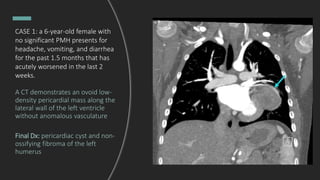

CASE 1: a 6-year-old female with

no significant PMH presents for

headache, vomiting, and diarrhea

for the past 1.5 months that has

acutely worsened in the last 2

weeks.

A CT demonstrates an ovoid low-

density pericardial mass along the

lateral wall of the left ventricle

without anomalous vasculature

Final Dx: pericardiac cyst and non-

ossifying fibroma of the left

humerus